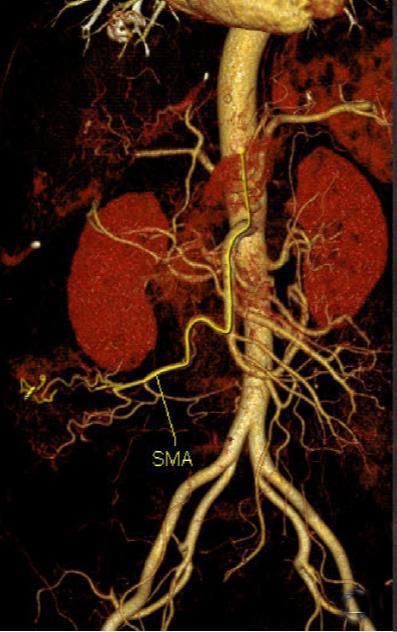

• 计算机体层摄影血管造影在腹腔镜结肠癌根治术前评估中的应用效果

摘要:目的 分析计算机体层摄影血管造影(CTA)在腹腔镜结肠癌根治术前评估中的应用效果。方法 回顾性分析2021年1月-2024年2月于该院接受腹腔镜结肠癌根治术的120例患者的临床资料。其中,60例行常规腹部CT和CTA,60例行磁共振成像(MRI)。以术后病理为金标准,判断CTA对临床T分期与术后病理的一致性,以及评估肿瘤是否侵犯肠系膜血管和周围组织的准确度。结果 术前CTA诊断T分期的准确率为95.00%(57/60),一致性好(Kappa = 0.925,P < 0.05);术前MRI诊断结肠癌T分期的准确率为98.33%(59/60),两者比较,差异无统计学意义(χ2 = 0.26,P > 0.05)。CTA预判肿瘤是否累及肠系膜上动脉、肠系膜上静脉、肠系膜下动脉、肠系膜下静脉、腹主动脉、肾动脉、肾静脉和脾动脉等血管,与术后病理的一致性好。特别是在预测肠系膜血管受累方面,CTA的敏感度为94.44%,特异度为95.83%,准确度高达95.00%。结论 对于行腹腔镜结肠癌根治术的患者,术前CTA不仅能清晰地显示结肠癌T分期,还能揭示肠系膜血管的走行和变异,以及肿瘤与周围组织的关系和侵犯程度,从而为手术规划提供强有力的支持,确保了腹腔镜手术的安全性,减少了不必要的手术风险。